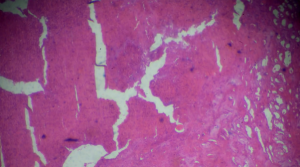

Figure 2: Kidney adenocarcinoma biopsy under light microscopy